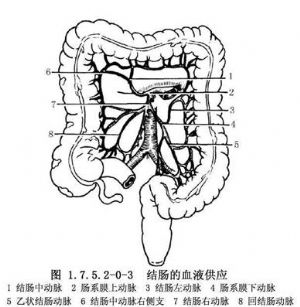

右半結腸的血液供應(圖1.7.5.2-0-3)來自腸繫膜上動脈分出的結腸中動脈的右側支、結腸右動脈和回結腸動脈。約25%病人無結腸中動脈,而由結腸右動脈的一支代替,有的病人有兩條結腸中動脈。橫結腸的血液供應來自腸繫膜上動脈的結腸中動脈。左半結腸血液來自腸繫膜下動脈分出的結腸左動脈和乙狀結腸動脈。靜脈與動脈伴行,最終注入門靜脈。有的結腸左動脈與結腸中動脈之間無吻合,也很少有邊緣動脈,此處稱Roilan點,手術時應加注意。淋巴管也與血管伴行,經過腸繫膜上、下動脈根部淋巴管至腹主動脈旁淋巴結,最後注入胸導管。因此,在根治結腸癌時,須將該部結腸動脈所供應的整段腸管及其系膜全部切除。